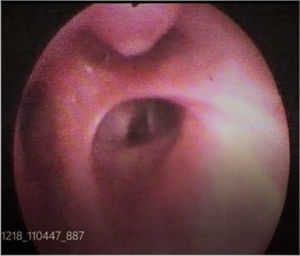

A 48-year-old male presented with recurrent hemoptysis for last three years without any other respiratory symptoms. He had two episodes of massive hemoptysis requiring hospitalization. He was a lifelong non-smoker without any significant past history. Computed tomography of the chest, performed on multiple occasions, was normal. He had undergone flexible bronchoscopy twice, which was reported to be normal. Flexible bronchoscopy, performed at our centre, demonstrated a nipple-like projection at right upper lobe apical segment opening (Fig. 1). A forceps biopsy was attempted, which led to blood spurt, and the patient had profuse bleeding (Video 1). A diagnosis of endobronchial dieulafoy's lesion was made. Subsequently, the Argon Plasma Coagulation application was performed, which led to the stoppage of bleeding.